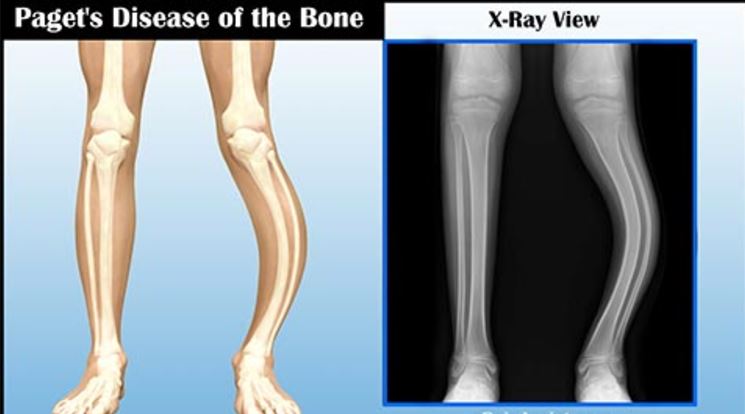

Paget Hastalığı Radyolojik Bulgular

Paget hastalığının derecesi ve yaygınlığı radyolojik inceleme ile fark edilebilir. Bu yüzden kemiklerin radyolojik incelemesi hastalık için önemlidir. Çekilen filmlere göre hastalığın çeşitli evrelerindeki süreçler gözlemlenebilmektedir. Kemiklerin erime sürecinde yapılan radyolojik bulgular belirsiz olmaktadır. Genelde uzun kemiklerin kenarları ve yüz kemiklerinde bölgesel kemik erimesi olarak görülmektedir. Kemik yapım işlemi başladıktan sonra radyolojik bulgular kendini göstermektedir. Sonradan meydana gelen kemiklerin yapısı oldukça biçimsiz ve kabadır.